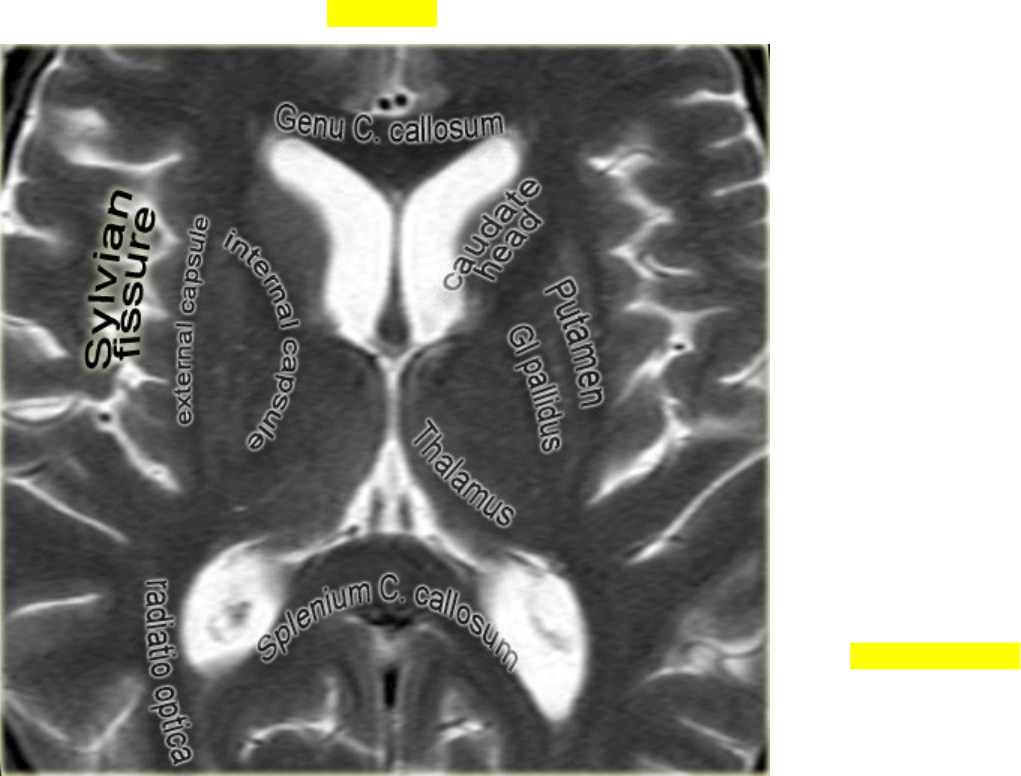

ANATOMIA – Tálamo

· Neste nível, os gânglios da base são vistos.

· As duas linhas escuras medialmente ao tálamo são as veias cerebrais internas.